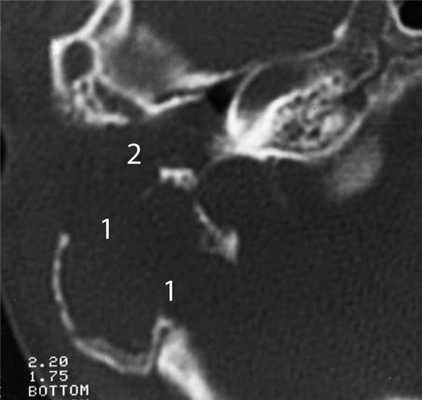

Частым проявлением опухоли височной кости, как было сказано выше, является ее распространение в наружный слуховой проход, что находит свое отражение и на КТ. При небольших размерах полипозного новообразования на КТ в просвете наружного слухового прохода визуализируется образование, исходящее из барабанной полости или проникающее в слуховой проход через его разрушенную стенку (рис. 2). Рисунок 2. Лангергансоклеточный гистиоцитоз. Коронарная проекция правой височной кости. В наружном слуховом проходе определяется полипозное образование (1), на уровне которого верхняя стенка НСП деструктивно изменена. Нарушена пневматизация среднего уха (2). Большой «полип» проявляется на КТ полной обтурацией воздушного просвета слухового прохода мягкотканным образованием (рис. 3). Рисунок 3. Рабдомиосаркома. Аксиальная проекция левой височной кости. Отсутствует пневматизация костного устья слуховой трубы и барабанной полости (1). Просвет наружного слухового прохода обтурирован мягкотканным полипозным образованием (2). Деструкция задней стенки барабанной полости и наружного слухового прохода (3). При анализе данного КТ-признака следует учитывать, что истинные полипы, встречающиеся при хроническом гнойном среднем отите, в отличие от опухолей имеют излюбленную локализацию и чаще всего исходят из верхних отделов барабанной полости.